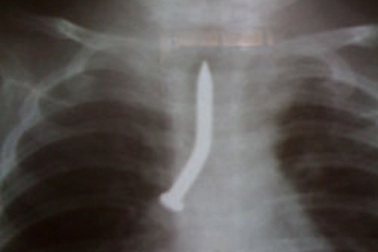

Nuốt đinh vít, bé 2 tuổi tử vongNhập viện trong tình trạng tím tái ngưng tim ngưng thở, X-quang cho thấy cây đinh vít nằm ở góc phế quản khiến phổi trái bệnh nhân gần như xẹp hoàn toàn. Dù bác sĩ đã tận tâm cứu chữa nhưng bệnh nhân không thể qua được nguy kịch.